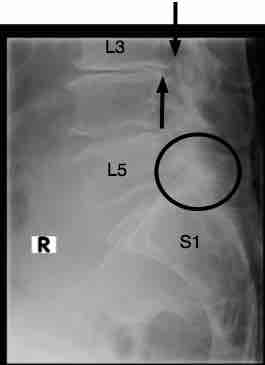

Notice the retrolysthesis of L3 on L4. There is marked disc degeneration, and the vertebra has subluxated posteriorly; it's circled.

Notice too the extreme facet degeneration at L5-S1 (circled).

See the nasty little dagger protruding into the IVF from the body of L3? It's arrowed below.